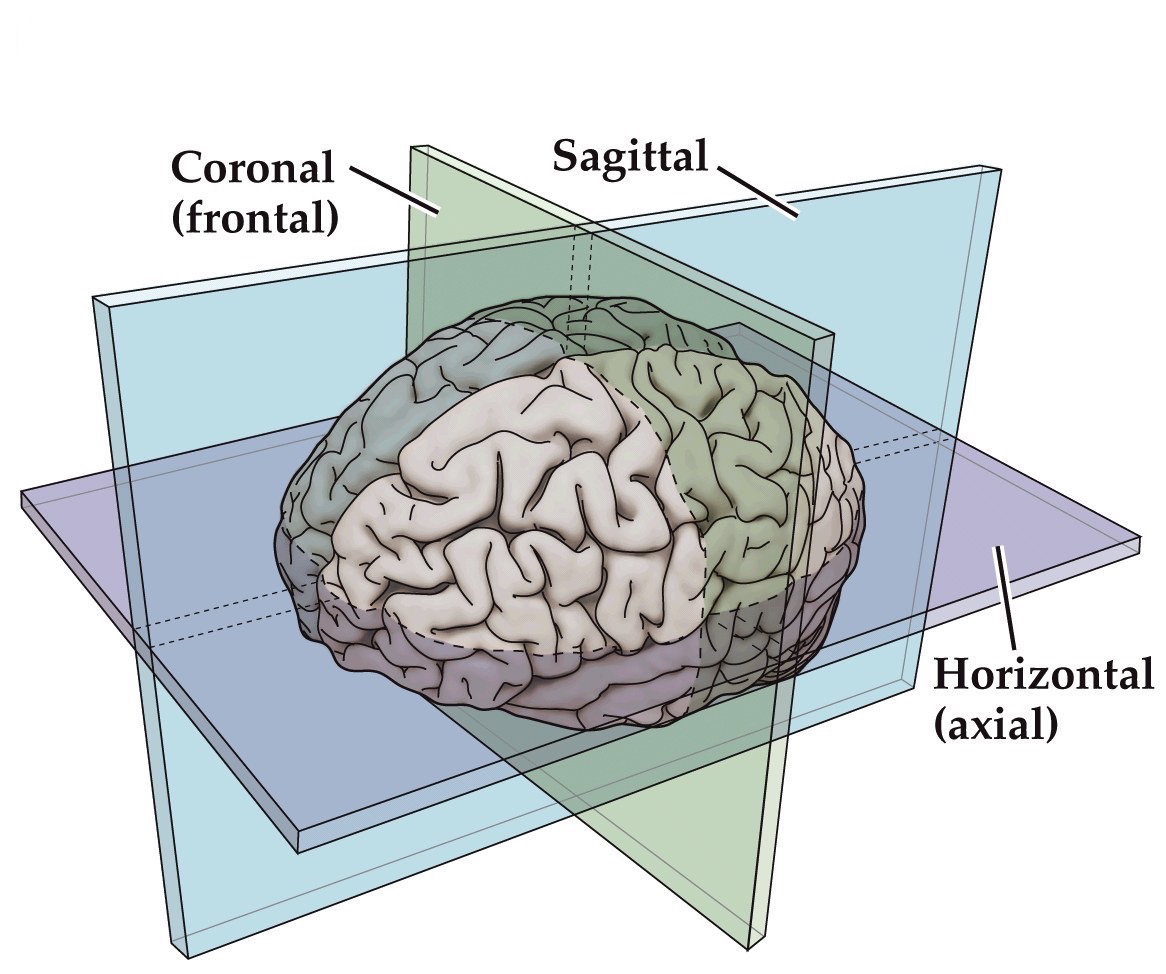

Anatomical terminology for CNS locations

Anatomical terminology for the three axes of the brain